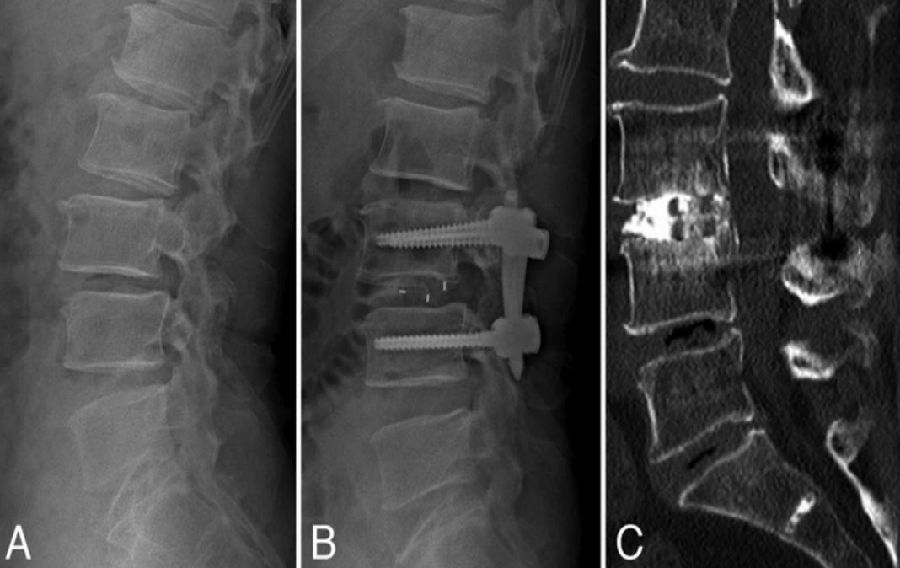

八、医源性不稳定(0.88%)

发生率0.6%,明显低于开放式手术,小关节突关节损伤是主要原因。上腰椎(L1~L3)病变、存在狭窄椎板和脊柱矢状面失衡的患者减压过程几率更高。

病例(关节突损伤)

男,52岁。

主诉:腰痛20余年,双下肢疼痛10余年,加重4天。

查体:双侧直腿抬高试验及加强试验(-),双侧膝腱反射及跟腱反射未引出,Babinski征(-)。

思考及建议

使用磨钻从棘突基底部与上椎板下缘交界处切开

术前CT测量关节突切除范围

L3-4及以上节段,对侧入路切除椎间盘